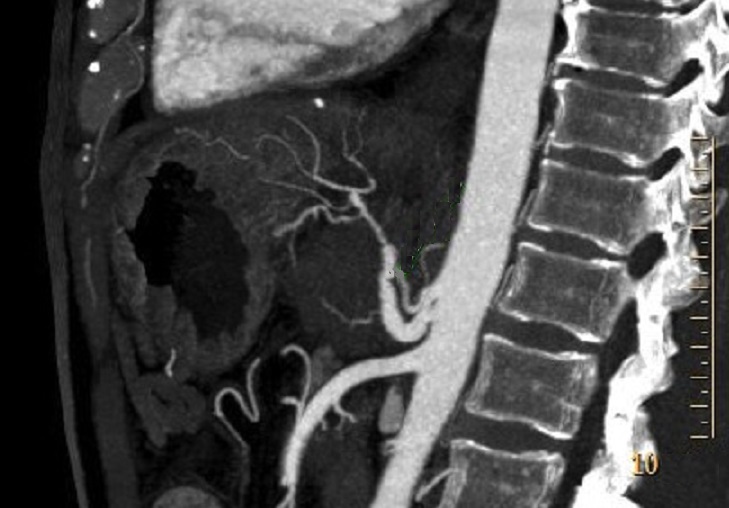

Image radiologique de TDM a

multibarette avec coupe tres fine millimetrique a

difference temps ce qui donne de image

angioscannographique arterielle en 2D . Dans ce cas

c'est image d 'engainement vasculaire d'une

adenocarcinoma du pancreas . Image recevoir

est tres nette comme une arteriographie en 2D . |